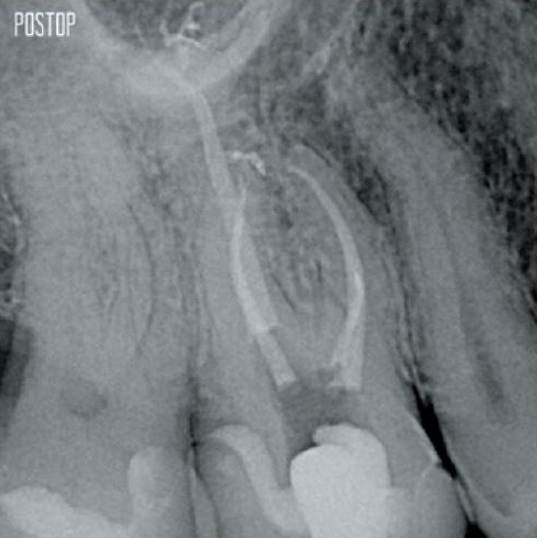

Photos courtesy of Dr. Ahmed Salman

More dentin preserved. Appropiate shaping, irrigation, and obturation ensured.